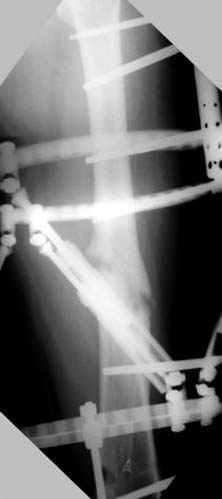

Djoldas Kuldjanov 23 Ноябрь 2004, 18:21

пластическая модель; и коррекция бедра аппаратом Илизарова.

Имею другие снимки тоже, получится как отчет о моей работе.